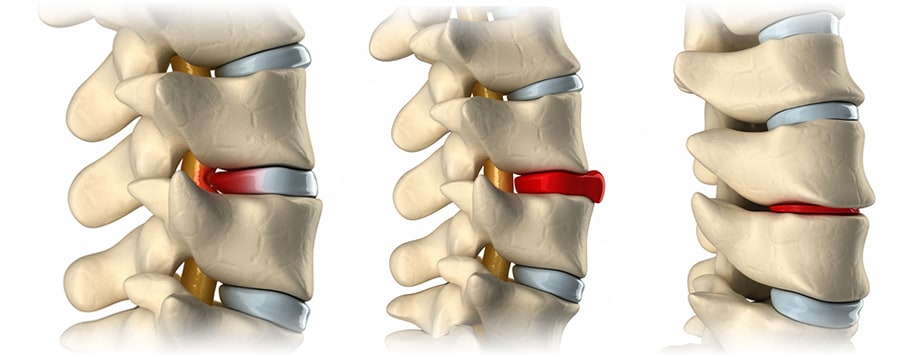

허리디스크란 척추뼈 사이에 있는 디스크가 손상되어 신경을 압박하는 질환을 의미합니다. 디스크는 척추뼈 사이의 충격을 흡수하고 척추의 움직임을 부드럽게 해주는 역할을 하는데, 이 디스크가 손상되면 신경을 압박하여 통증, 마비, 감각 이상 등의 증상이 나타납니다.

또한 나이가 들면서 디스크의 수분 함량이 감소하고 섬유륜(※섬유륜 이란? 척추 사이 원반의 바깥 부분을 고리처럼 이루는 섬유 연골과 섬유 조직을 의. 이것이 약해졌을 때 속질핵이 빠져나가 척추 원반 탈출증을 일으킬 수 있다.)이 약해지면서 허리디스크가 발생할 수 있습니다.